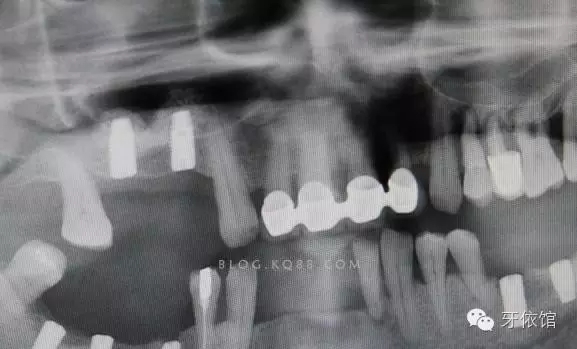

植體的平行度很好

深度也很滿意。

術后X光片